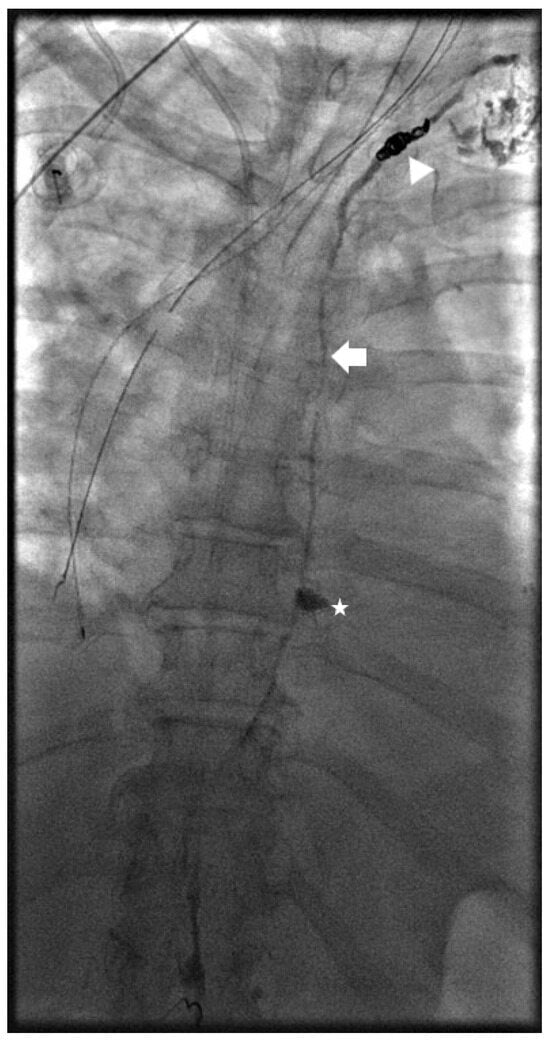

Management strategies for chylous ascites (CA) encompass a range of interventions, with a growing trend towards minimally invasive techniques. Intranodal lymphangiography (INL) is a primary management step for chylous ascites (CA) following conservative treatment failure. The procedure involves directly injecting contrast material (typically lipiodol) into lymph nodes to visualize the lymphatic system. INL serves as both a diagnostic tool and a potential standalone treatment (Figure 1). Aly et al. employed a conventional bilateral lymphangiography approach, using a minimum of 6 mL of lipiodol on each side [20]. This contrast with other studies using larger volumes, such as Verhaeghe et al., who reported a mean of 29.8 mL using it as the only treatment agent [21]. The technical success of INL is consistently high, approaching 100% in most studies. Technical success is generally defined as successful needle introduction and subsequent lymphatic opacification. However, injection methods, rates, dilution, and quantities of lipiodol vary among practitioners, reflecting the lack of standardization in CA management.

Following INL, embolization is often performed to address identified leak points. This process typically involves accessing the lymphatic system through a larger needle (20–22 G) under imaging, confirming proper positioning by flushing with 5% dextrose, and then employing various embolization techniques (Figure 2). The most common embolic agent is n-butyl cyanoacrylate (nBCA) in varying dilutions with lipiodol. Proper contrast opacification is crucial to identify leak points and exclude potential shunts.

Figure 1. Spot image from an intra-nodal lymphangiogram for a 39-year-old patient with traumatic chylous ascites after retroperitoneal lymph node dissection. Lipiodol is seen filling the retroperitoneal lymphatics (arrowhead) and leaking into the peritoneal space (arrows).

Figure 2. Spot image the same patient in Figure 1 with a 22-gauge needle placed under fluoroscopy into the site of the lymphatic leak (arrow) prior to embolization.